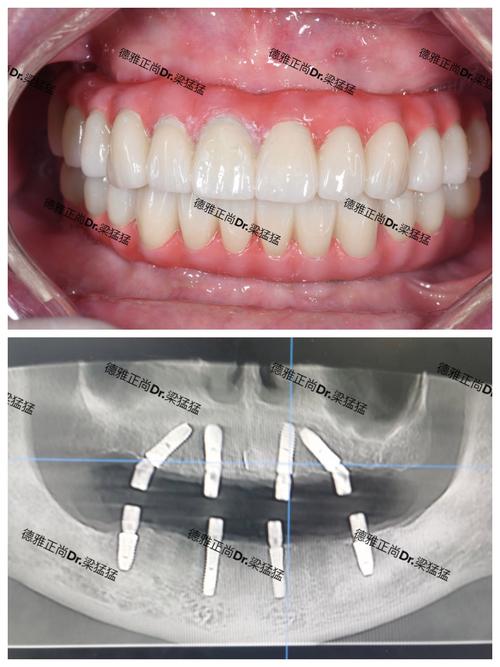

种牙流程的规范化和透明化也是苏州种牙的优势之一,正规的种牙机构通常会遵循“术前检查—方案设计—手术植入—戴牙冠—术后维护”的标准化流程,术前检查包括口腔CT、血常规等,评估骨量、骨质及全身健康状况;方案设计阶段,医生会结合患者需求和经济条件,推荐合适的种植体品牌(如瑞士ITI、瑞典Nobel、韩国Osstem等)和牙冠材料(全瓷牙、烤瓷牙等);手术过程一般在局部麻醉下进行,微创技术可缩短手术时间(30分钟-2小时不等),术后疼痛感较轻;戴牙冠通常在术后3-6个月,待种植体与牙槽骨结合后完成,最终效果兼顾功能与美观。